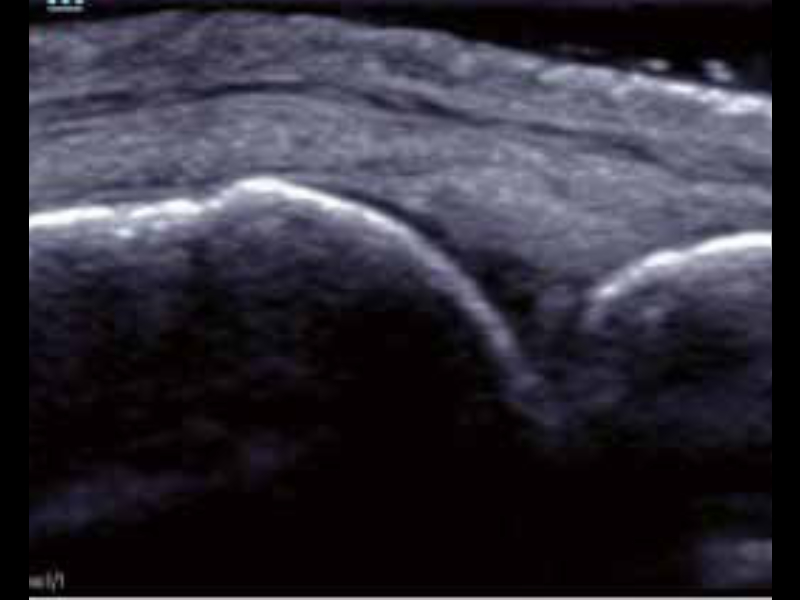

Kość ramienna w trybie B

• zeus-fig5-2-2-uk

Staw śródręczno-paliczkowy

• zeus-fig5-2-3-uk